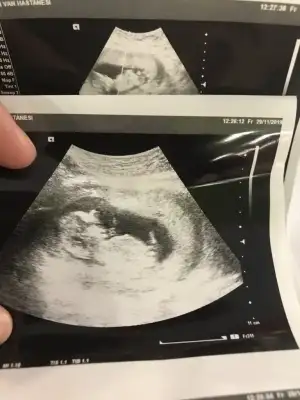

Erkek diyorum kaç haftalık usg

13. Haftalık 11 ve 12. Haftalıkken doktora gitmedik kontrolümüz 13. Haftaya denk geldi o yüzden bu başka da var ama net değil ki atayım ben yine deerkek gibi başka usg var kaç haftalık

erkek gibi başka usg var kaç haftalık